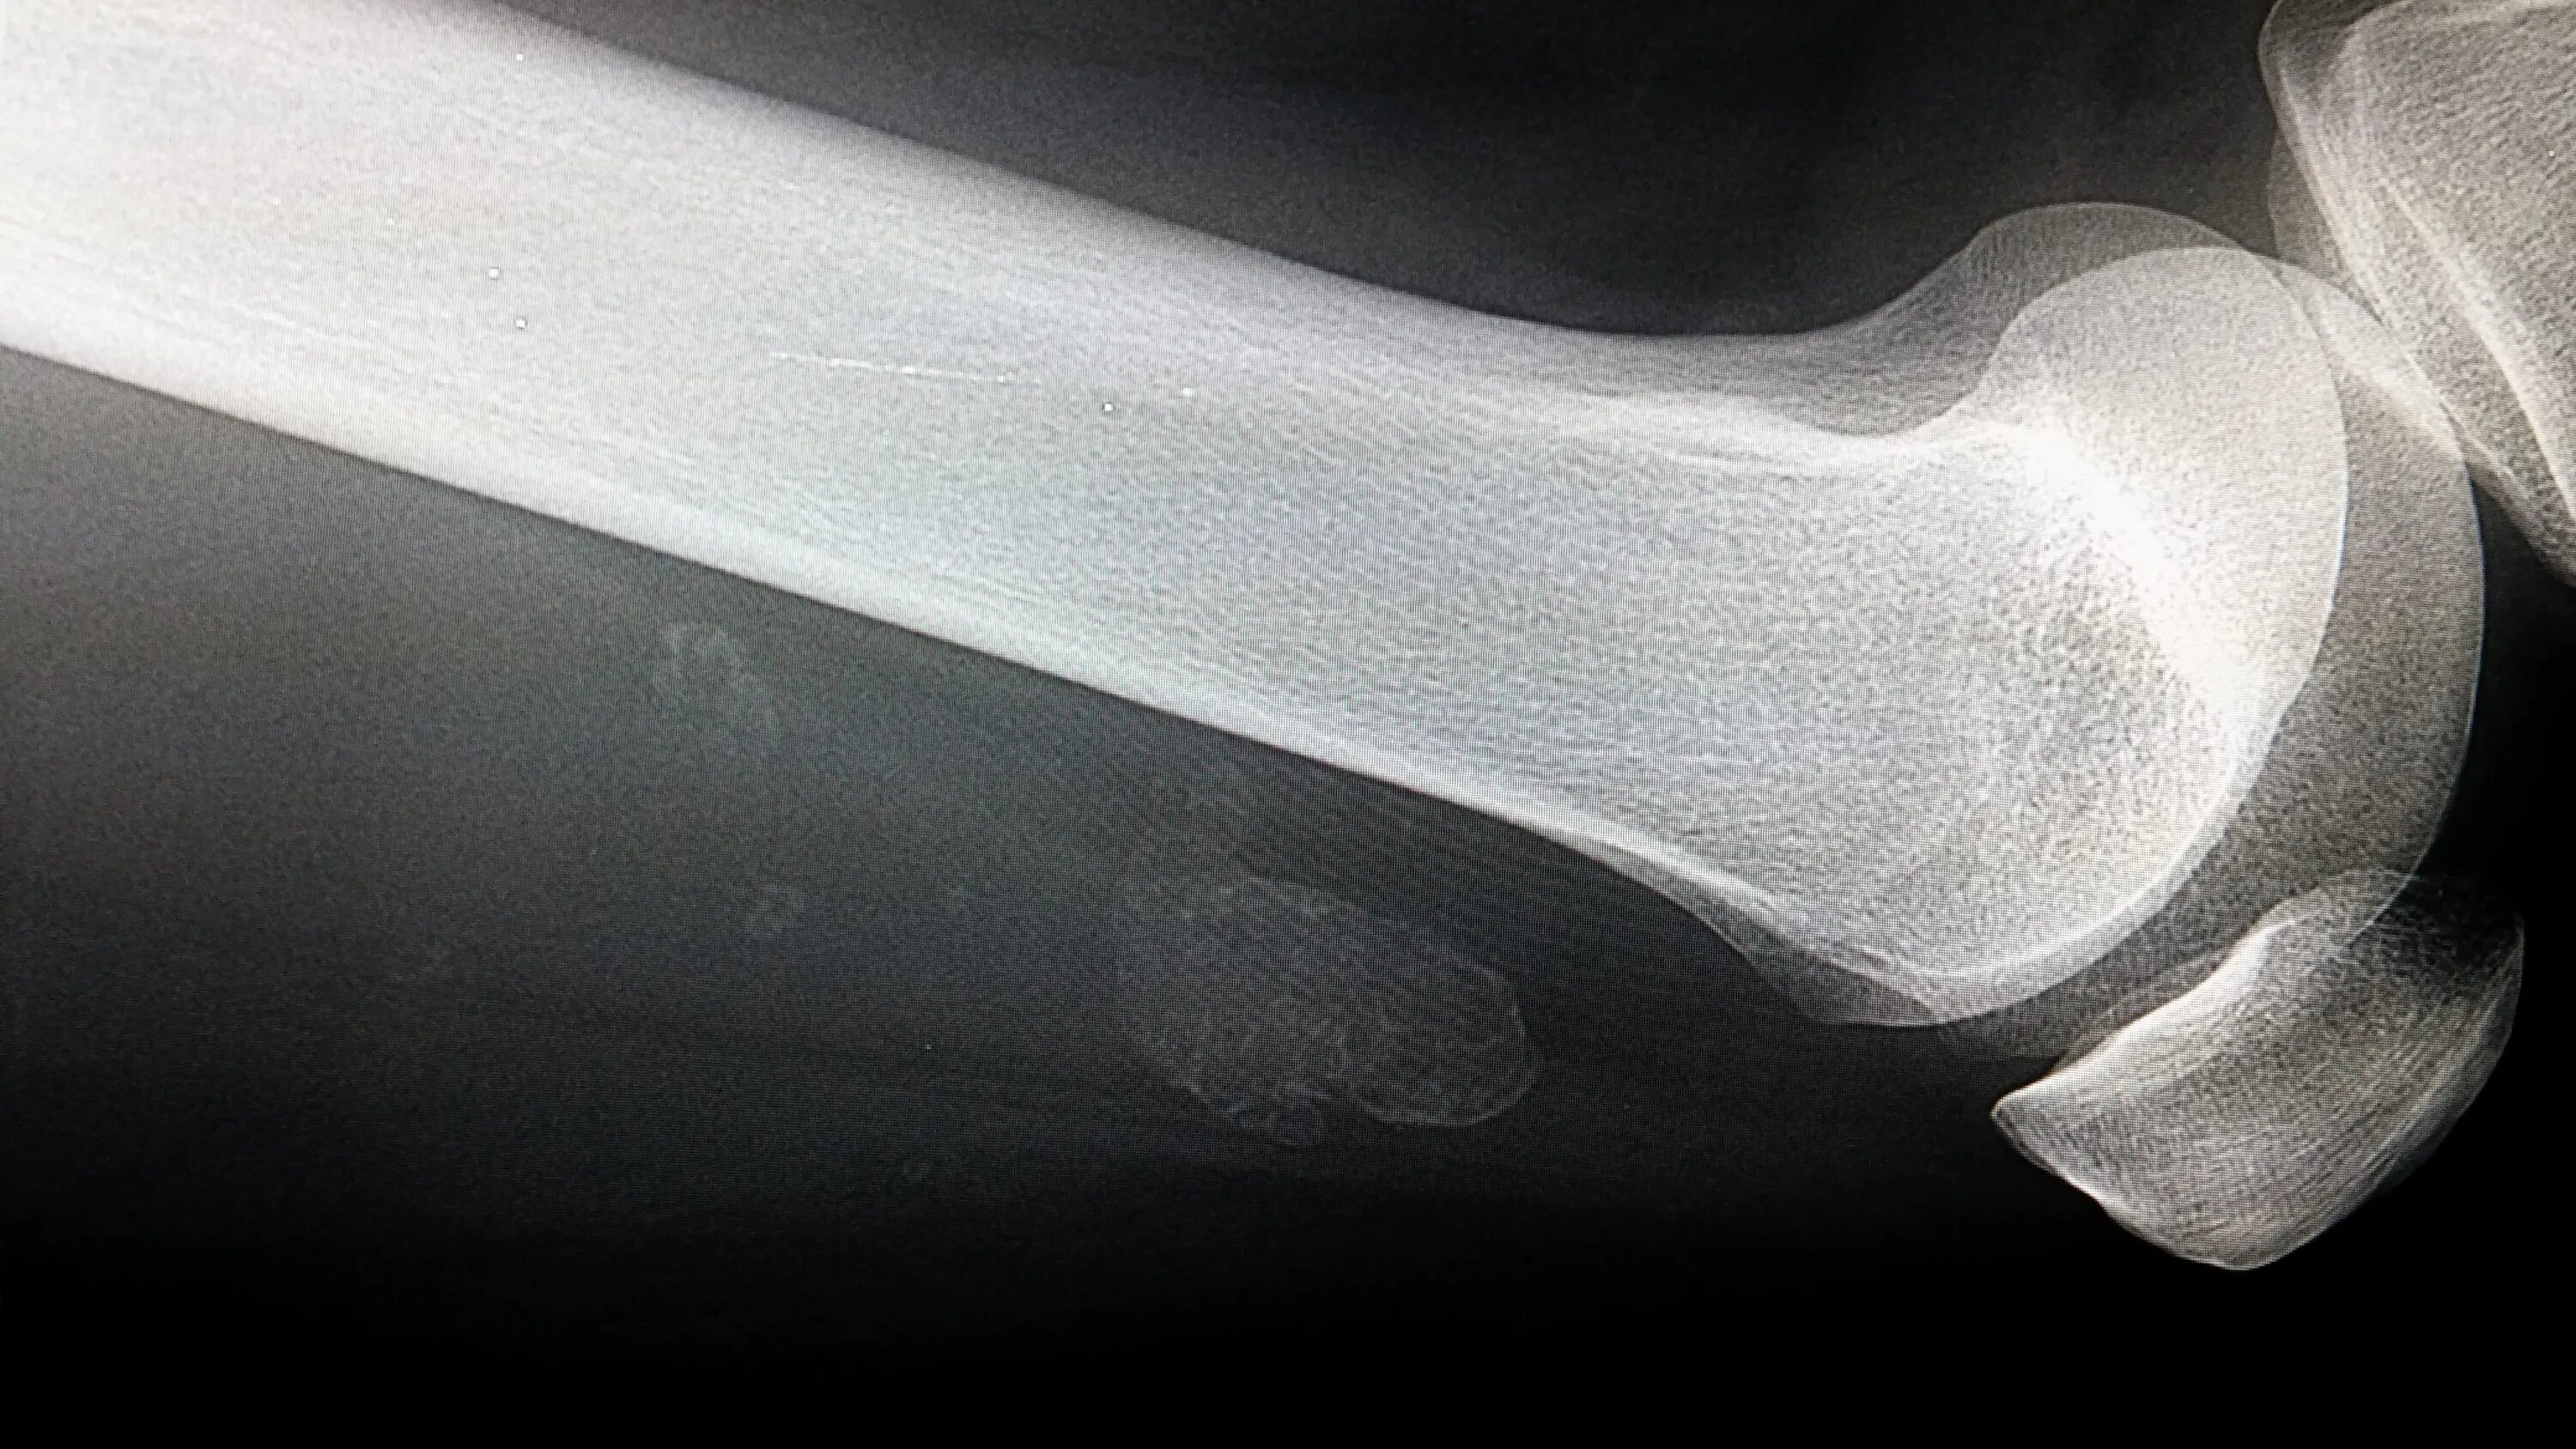

Обызвествление сухожилий мышц